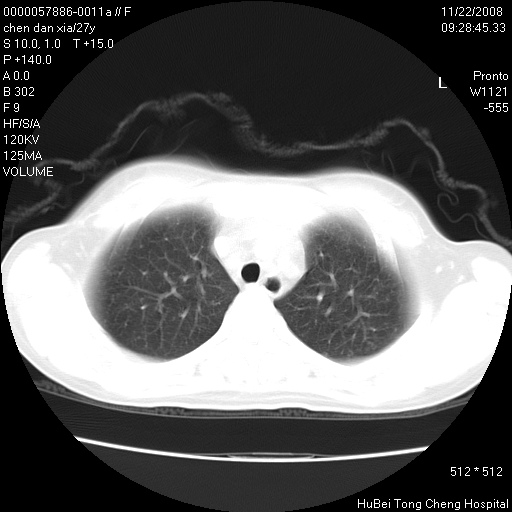

标题: CT16752:F,27Y。发热咳嗽20余天,伴盗汗。 [打印本页]

标题: CT16752:F,27Y。发热咳嗽20余天,伴盗汗。

考虑双肺粟粒性肺tb,右侧胸膜增厚.

气管前腔静脉后淋巴结肿大 右肺门纹理模糊

淋巴结核?

右下肺见片絮状影,两肺野内分布不均的小结节影,结核并肺内播散可能性大,建议结合实验室检查 .

右下肺纹理模糊;纵隔可见肿大淋巴节;右心缘旁结节,边缘光滑,纵隔窗病变范围较肺窗明显小,首先考虑右下肺结核,不排外淋巴瘤

双肺纹影普多,部分呈网状,支炎或淋巴管炎?

纵隔内淋结肿

局部胸膜增厚

下肺结节,结节内钙化,肺门纵隔淋巴肿大 结核可能性大

似有粟米状结节。考虑粟粒型肺结核?

1)考虑两肺感染性病变。2)纵隔淋巴结肿大。